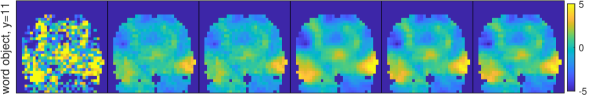

4.2.3 Prior simulation

To better understand the meaning of the different priors in practice, Fig. 4 displays samples from the spatial priors using the estimated hyperparameters for the first regressor of the different datasets. The M and ICAR priors produce fields that vary quite rapidly, while the second order priors give realizations that are more smooth. For the word object dataset we note that the short estimated range for M gives a sample with much faster variability than the sample from ICAR, which looks unrealistically smooth. This illustrates the problem with using the infinite range ICAR prior for a dataset where the inherent range is much shorter.